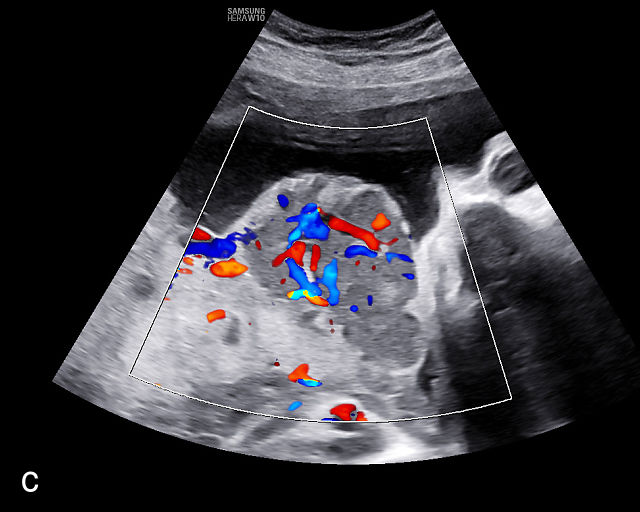

Placental chorioangiomas

The typical sonographic appearance of a chorioangioma on grayscale ultrasound is a well-circumscribed mass arising from the fetal surface of the placenta, protruding into the amniotic cavity, and distinctly separate from the placenta (Figure 12; Video 7). These tumors are most commonly located near the umbilical cord insertion site on the placenta. Sonographically, they may appear hypoechoic or hyperechoic and are often heterogeneous, with possible calcifications, hemorrhage or infarction visible within the mass.9 The appearance of these masses may change over time.141 Color flow Doppler imaging typically reveals vascularity within the tumor, showing low-resistance vessels and arteriovenous shunts (Figure 12c–e; Video 7).9 These shunts are believed to contribute to fetal complications such as high-output cardiac failure, anemia and hydrops.141 Three-dimensional ultrasound may be helpful in assessment of the mass.146 Importantly, the differential diagnosis includes placental hemorrhage, and color flow Doppler is essential to assist in making the diagnosis.

12

Grayscale (a,b), color Doppler (c,e) and power Doppler (d) images of chorioangiomas, showing heterogeneous masses protruding from the placental surface.